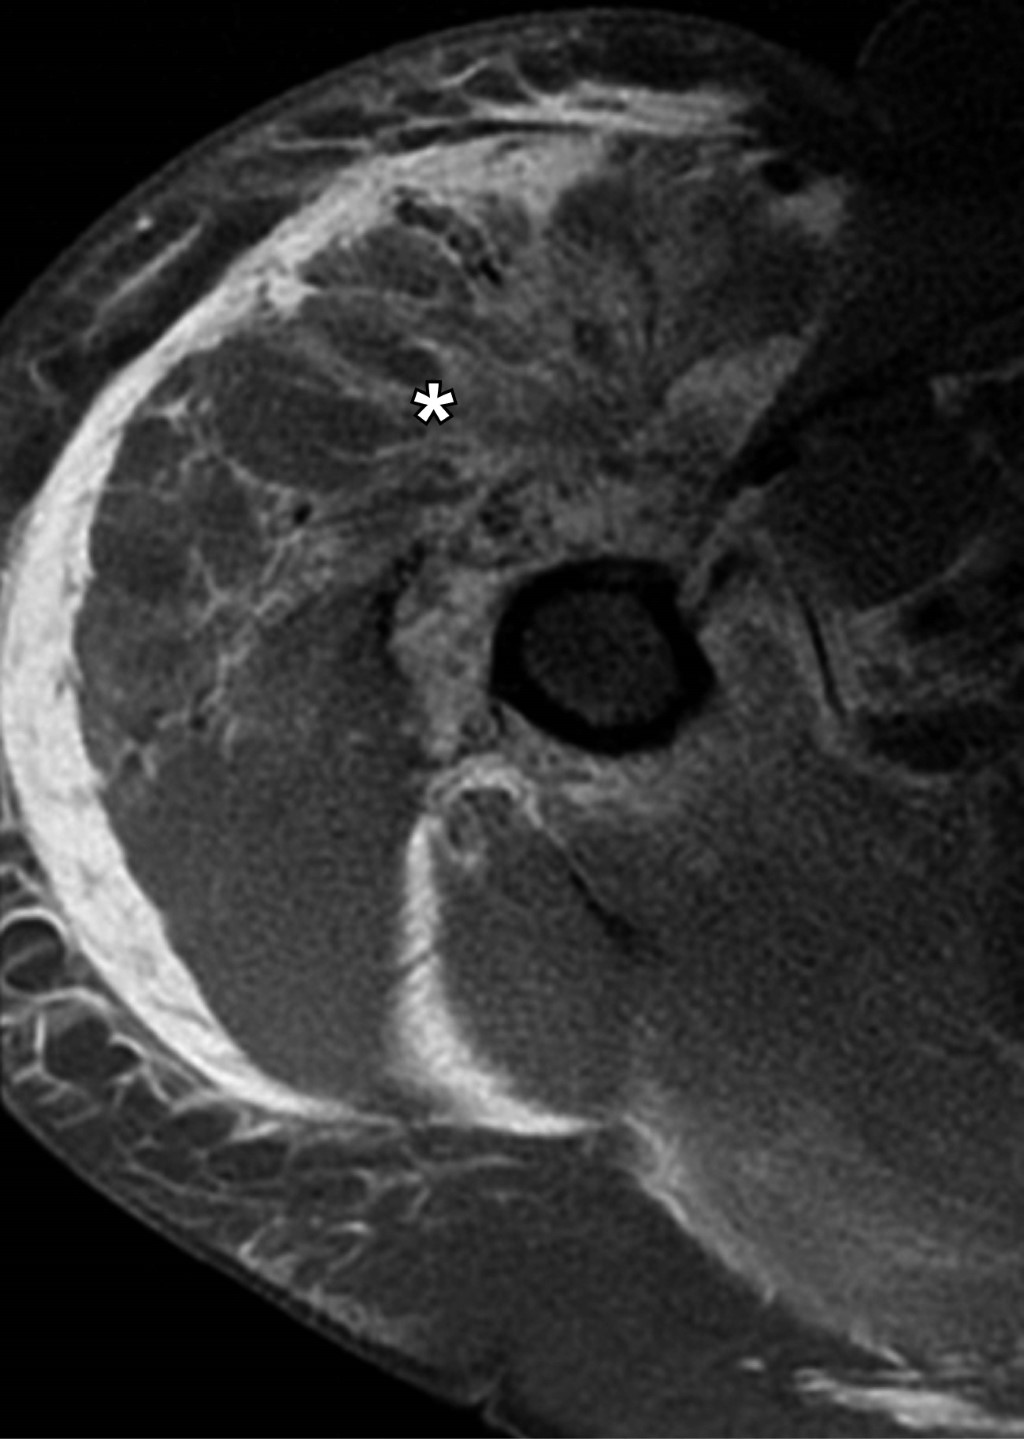

Multifragmentary proximal humerus fracture, the importance of MRI assessment

Proximal humerus fractures represent 45 to 50% of humeral fractures, and the main risk factors are falls, age, osteoporosis, and high-impact sports. The initial diagnostic method for assessing bone structures is radiography, which can be complemented with a tomographic study to assess the fracture line and associated characteristics. In multi-fragmentary fractures with complex lines, the trend of using magnetic resonance imaging is on the rise, as it allows the evaluation of myotendinous and ligamentous structures, which are limitedly evaluated in studies based on ionizing radiation.

Figure 1